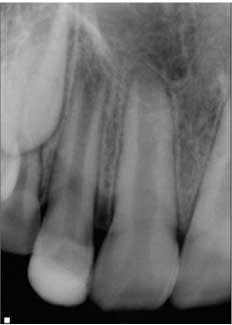

At the second visit, the tooth was anesthetized with an anesthetic that had no vasoconstrictors (to increase the likelihood of getting a blood clot in the tooth, Petrino et al., 2010), isolated, and accessed. The canals were irrigated with 20 ml of 5.25% NaOCl. After irrigation, the canal system was dried and a small, stainless steel hand file was used to lacerate the periradicular tissue to induce bleeding into the canal system. Once there was evidence of blood flow back into the canal, Collaplug (Zimmer Dental, Carlsbad, Calif.) was placed into the canal system to help create a barrier at the coronal portion of the canal. After formation of the blood clot, white MTA was condensed on top of the Collaplug to seal the canal system. The tooth was temporized, and the patient was instructed to return to his general dentist for restoration of the access (Fig. 2).Fig. 2: Tooth No. 7 after second visit showing placement of the MTA barrier.The patient was placed on recall and returned approximately eight months following treatment. The patient and parent reported that the tooth was not restored, but had been asymptomatic. Clinically, the tooth was asymptomatic, and radiographs showed signs of resolution of the apical radiolucency, increased thickness of the root walls, and apical closure. The patient was encouraged to have the access restoration restored. (Fig. 3) The patient returned at 15 months for his next recall examination, and the tooth had a permanent restoration. Clinically, the tooth was asymptomatic, and radiographs showed evidence of apical bone healing, increased thickness of the root walls, and apical closure. (Fig. 4)